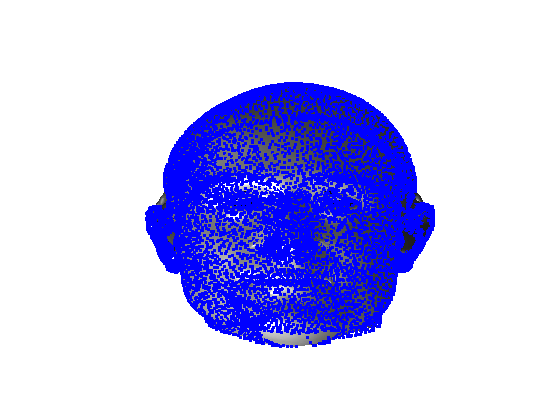

Following this, OSNR ICP iterates over a set of decreasing mesh stiffnesses (typically 10), until the registration between the template and the scan is below some error or a maximum number of iterations is reached. Figure 28 shows a selection of template warp results. The template appears to be accurately warped onto the scan, at least in the normal direction of the surfaces, it is not possible to see error tangential to the surface. Furthermore, we have noted errors on some scans on the ears. To improve these we need a method of automatically landmarking the ears, which is an area for further work.

|

|

|

|

|

|

|

|

The first two modes of head variation are shown in figures 29 and 30. These include the cranial height / facial angle mode and the (almost) pure size mode, as seen in the sagittal profile model.